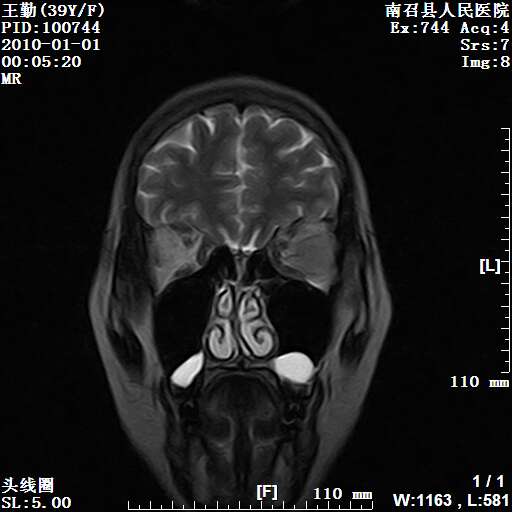

以下是引用随光逐影在2010-1-22 9:03:00的发言:[br]考虑左侧中颅窝(蝶骨翼区)脑膜瘤侵犯蝶骨翼并突入左侧眼眶。

以下是引用水过无痕在2010-1-22 14:55:00的发言:[br]一、定位:颅外占位;二、定性:恶性可能性大;三、组织来源:来源于左侧眼外直肌或其他部位;考虑为:横纹肌肉瘤>转移瘤>脑膜瘤.